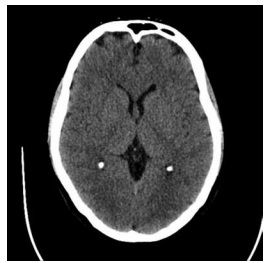

Homem de 62 anos, com histórico de hipertensão e

diabetes mellitus tipo 2, é admitido ao pronto-socorro

após episódio convulsivo tônico-clônico generalizado que não cessou espontaneamente. No hospital,

ele apresenta um novo episódio, seguido por estado

de consciência alterada sem recuperação entre os

eventos. Sua glicemia capilar está dentro dos limites

normais. O paciente é diagnosticado com status epiléptico convulsivo. Após administração de 20 mg de

diazepam intravenoso e dose de fenitoína (20 mg/kg),

as crises persistem. O EEG confirma atividade ictal

contínua. TC de crânio inicial a seguir.